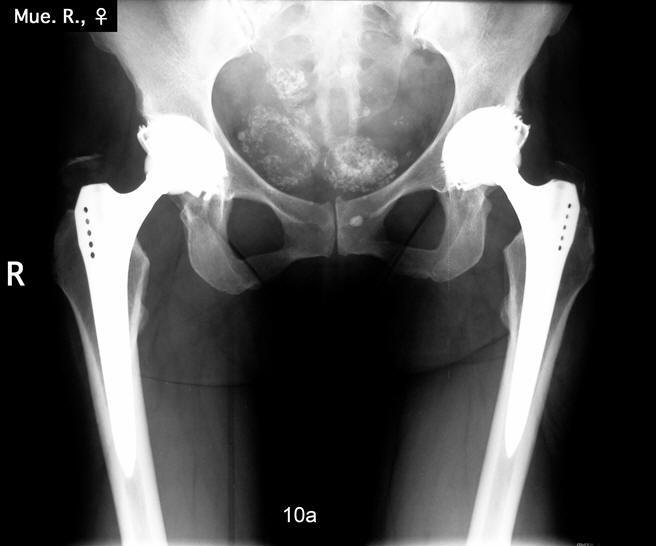

Beide

Hüftgelenke wurden in einer Operation ersetzt. Das Röntgen zeigt das

Ergebnis 10 Jahre postoperativ. Beide Hüften sind stabil im Knochen

verankert, die Patientin ist außerordentlich zufrieden.